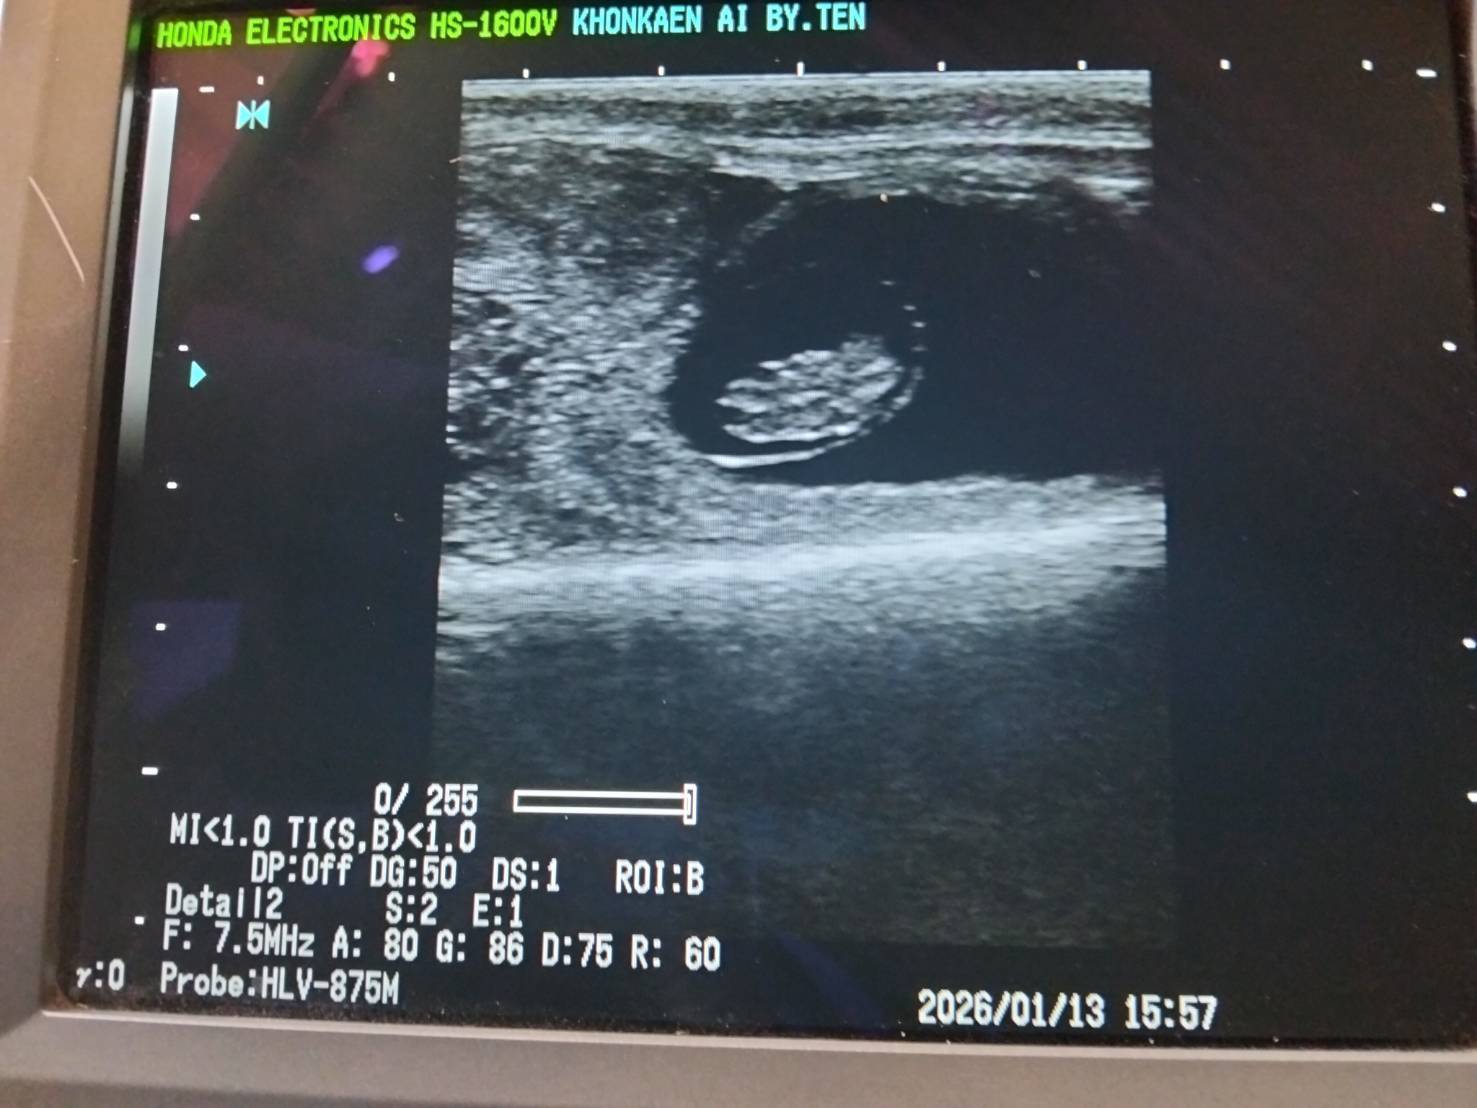

ศูนย์วิจัยการผสมเทียมและเทคโนโลยีชีวภาพขอนแก่น โดยสถานีพัฒนาเทคโนโลยีการผสมเทียมเมืองขอนแก่น1และ2 ลงพื้นที่ฟาร์มโคนม อำเภอเมือง จังหวัดขอนแก่น เพื่อปฏิบัติงาน ผสมเทียมโคนม, วัดประเมินรูปร่างโคนม, ตรวจท้อง, แก้ไขปัญหาระบบสืบพันธุ์โดยใช้ฮอร์โมนCIDR-B, ฮอร์โมน GnRH, ฉีดบำรุงวิตามินB12 และวิตามินAD3E และวัดน้ำหนักโค ให้แก่เกษตรกร